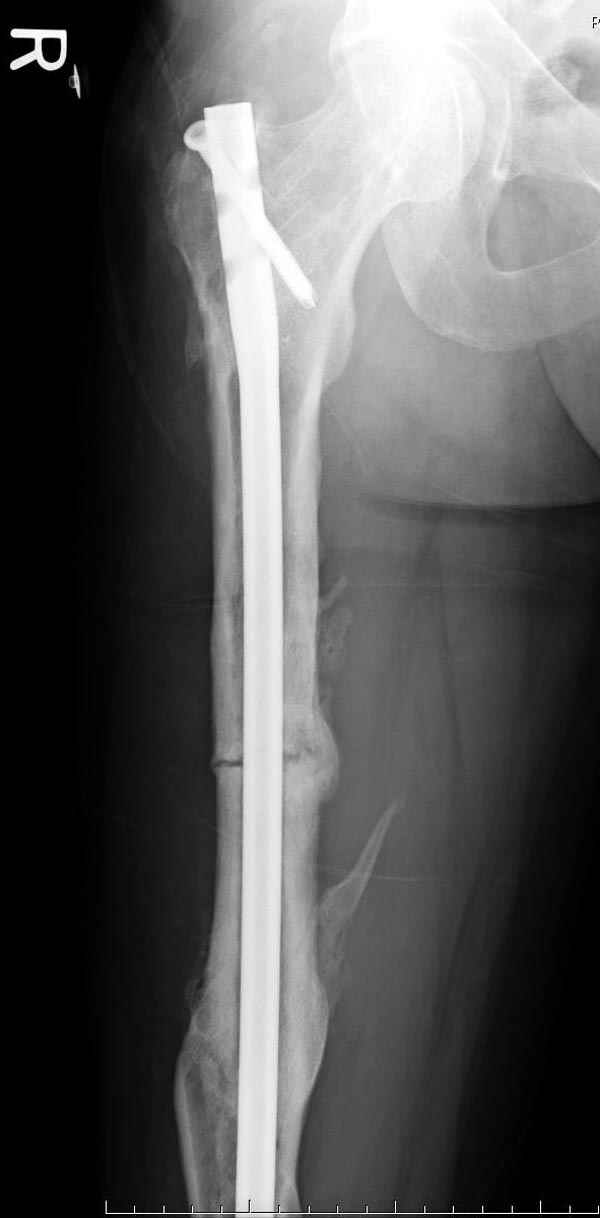

Мы не дождались “Happy End”, у больного IQ в пределах 70%, через 6 месяцев вернулся после небольшой травмы, споткнувшись получил перелом

того же бедра (рис №7).

На следующий день произвели интрамедуллярный остеосинтез: этапы во время операции (рис №8, №9)

и последующих снимках (рис №10, 11, 12, 13) перелом сростается и передвигается с полной нагрузкой.

При обзоре причин перелома, на снимке №2 обнаружили, что один из стержней аппарата наружной фиксации проходил только через передний кортекальный слой, что создало стрессовую зону на бедре и в результате перелом из-за незначительной травмы.